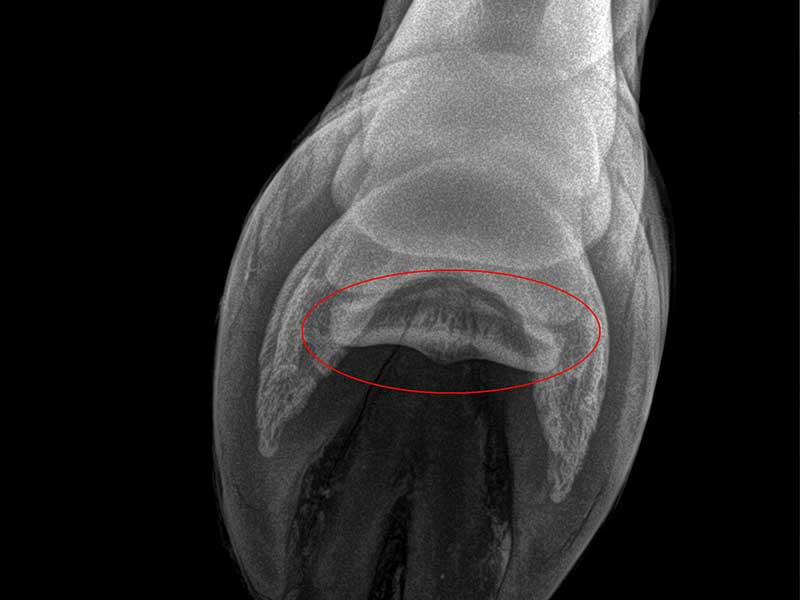

La radiología digital es una herramienta imprescindible en la valoración diagnóstica de muchos problemas equinos. En JOSE LUIS RUBIALES Veterinario trabajo con un equipo portátil de radiología digital de alta calidad, lo que permite obtener imágenes claras en muy poco tiempo y trabajar con una base mucho más precisa.

La radiología digital resulta muy útil cuando necesitamos obtener una valoración más precisa de una lesión o completar el diagnóstico de determinados problemas locomotores. Además, al tratarse de un sistema portátil, en muchos casos permite estudiar al caballo sin necesidad de desplazarlo.